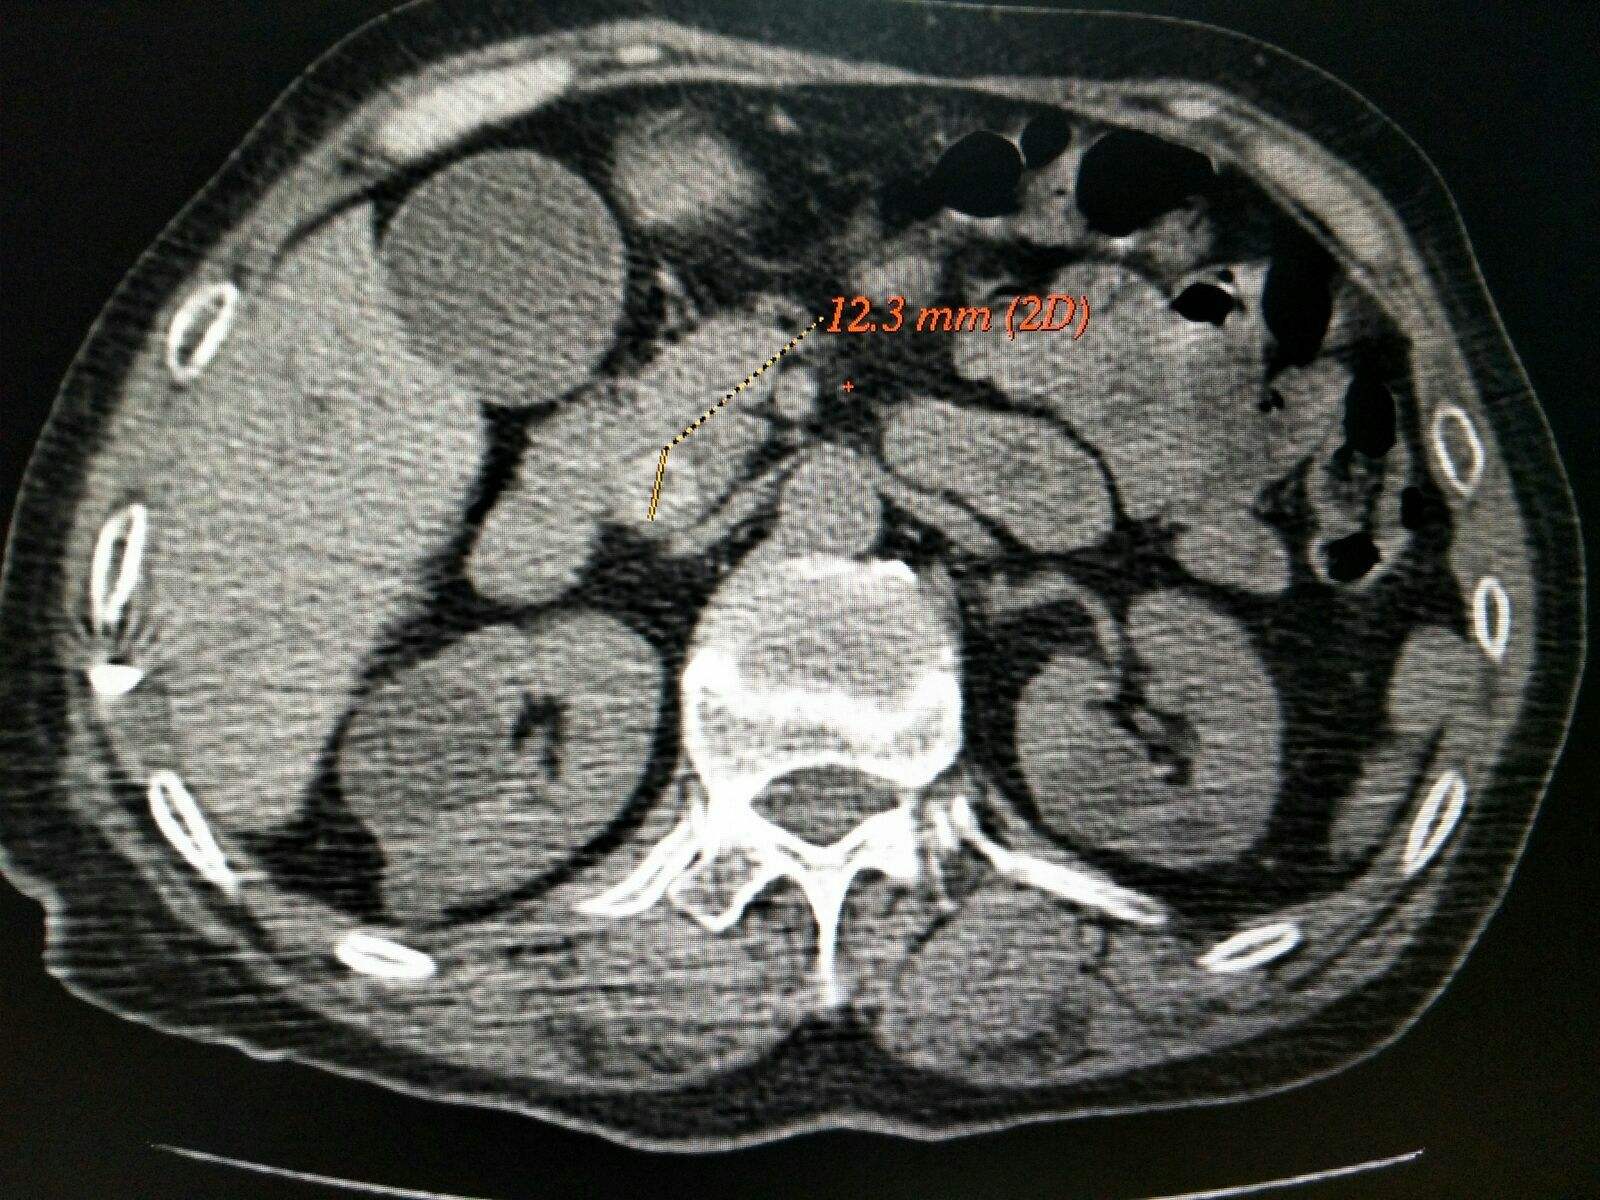

CT对胆总管扩张有很高的灵敏度,还可以判断上腹部疼痛和胆结石并发症的其他原因,常规CT检测胆总管结石的灵敏度约为80%,特异度约为90%,口服造影增强CT有更高的灵敏度,为92%。

CT检查是一种常见检查,尤其在判断腹部症状不明显的病人时很有用。但 CT若作为胆囊切除术前诊断胆总管结石的常规检查是不合理的,因为它的阳性预测值较低,且有一定的辐射。